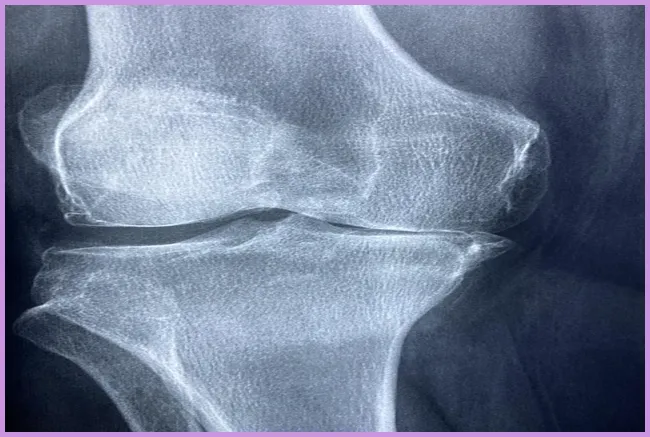

류마티스 관절염은 면역 시스템이 자신의 관절을 공격하여 염증을 발생시키는 자가면역 질환입니다. 이는 지속적인 통증과 불편함을 유발하며, 관절의 기능을 저하시킬 수 있습니다. 초기 단계에서는 일반적인 증상으로 시작하여 시간이 지남에 따라 악화될 수 있습니다. 이 질환은 주로 손, 발, 무릎과 같은 관절에 영향을 미치는 경향이 있습니다. 그렇다면 이 질환의 초기 증상은 무엇일까요?

관절염의 초기 증상 중에서도 가장 눈에 띄는 것은 관절의 통증입니다. 이 통증은 아침에 더욱 심해지는 경향이 있으며, 예를 들어 아침에 일어나서 발가락의 통증으로 인해 걷기가 힘들어질 수 있습니다. 이러한 증상은 해당 관절의 염증에 의해 발생합니다. 초기 증상이 나타났다면 전문가와의 상담을 통해 조기에 대처하는 것이 매우 중요합니다.